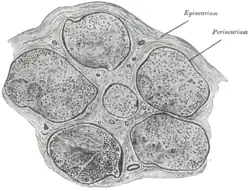

Die einzelnen ummarkten Nervenfasern werden durch sehr feine Bindegewebslamellen, das sogenannte Endoneurium, voneinander getrennt. Es besteht aus retikulären Fasern und einer Basalmembran.

Mehrere solcher Fasern werden durch das sogenannte Perineurium zu Faserbündeln (Faszikeln) zusammengefasst, das aus kollagenem Bindegewebe besteht.

Das Epineurium umhüllt schließlich den gesamten peripheren Nerv (d. h. mehrere Nervenfaserbündel) und fixiert diesen im umgebenden Gewebe.

Diese Bindegewebsumhüllung gibt den Nerven eine höhere Elastizität (durch elastische Fasern), schützt vor Druck und sie dient den Schwann-Zellen zur Ernährung, da in diesen Bindegewebslamellen die Blutgefäße verlaufen.